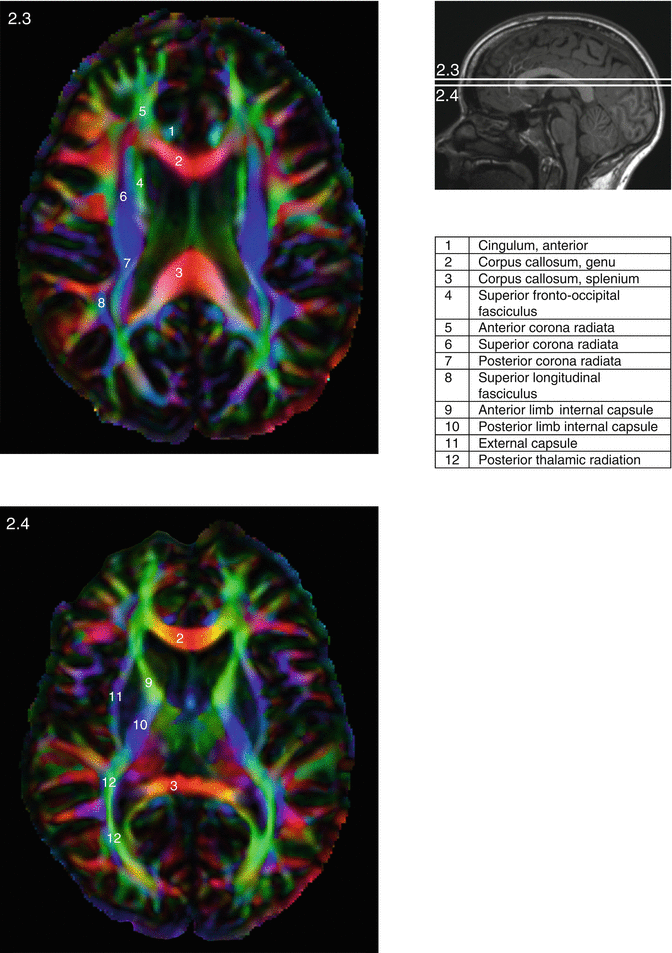

Pathophysiology Free FullText Microstructural Properties of Brain

From www.mdpi.com

Pathophysiology Free FullText Microstructural Properties of Brain Why White Matter Is White White matter, which lies beneath the gray matter cortex, is composed of millions of bundles of axons (nerve fibers) that connect neurons in. We explain why white matter matters. White matter provides the structural connectivity between gray matter regions throughout the brain, and the importance of. Gray matter and white matter do have different responsibilities, but both are essential for. Why White Matter Is White.